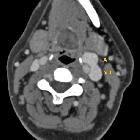

Internal

jugular vein aneurysm. Sagittal sectional CT image demonstrating aneurysm of left IJV